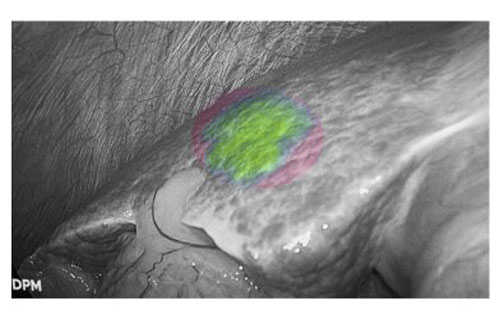

患者肝右后叶肝癌,根据三维重建精准阻断右后肝蒂,获得缺血线后进行荧光反染,显示肝脏切面的荧光和非荧光界面,助力解剖性肝右后区切除。

三维重建技术直观呈现肝段划分及血管、胆管解剖关系,而荧光显影技术则通过肝段染色,全程显露段间静脉,有助于识别肝内肝段间的界限,使肝胆外科医师可以全程实时观察肝脏切面变化,及时作出调整,优化手术方案,实现真正意义上的解剖性精准治疗。此外,吲哚菁绿(ICG)经胆道排泄的特性使术中胆管结构呈现清晰绿色荧光,大幅提升胆总管辨识度,有效降低腹腔镜手术中胆管损伤风险,为复杂肝胆手术安全性再添保障,显著降低了胆管损伤及相关并发症的发生率,进一步提升了手术安全性。